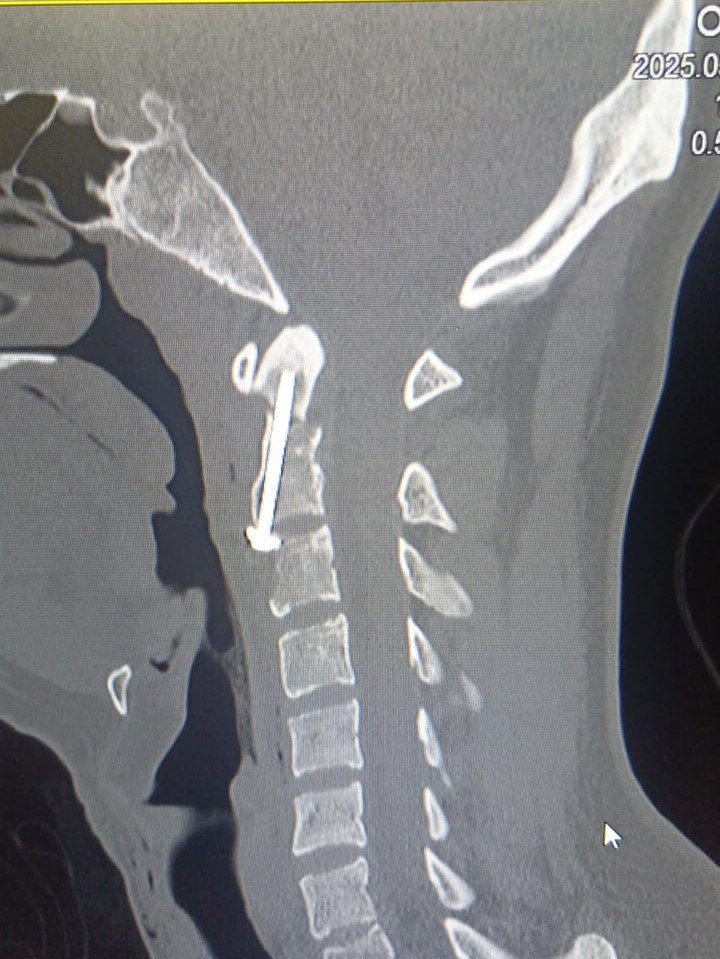

Ordu’da 17 Mayıs 2025 tarihinde gerçekleşen trafik kazasında Medical Park Ordu Hastanesi’ne getirilen Şimal Öktem’in yapılan tetkiklerinde, boyun omurga bölgesinde hayati tehlike arz eden bir odontoid (dens) kırığı tespit edildi. Hastanedeki tetkiklerde 20 yaşındaki Öktem’in vücudundaki kırıkların, omuriliğe zarar vererek felç veya ölüm riski oluşturabilen, üst servikal travmalar arasında yer alan yüksek enerjili kırıklar olduğu anlaşıldı.

Şimal Öktem’in kırığının, tıpta ’Tip 2 odontoid kırığı’ olarak sınıflandırılan ve nadir görülen bir durum olduğunu dile getiren Medical Park Ordu Hastanesi Beyin ve Sinir Cerrahisi Uzmanı Dr. Öğr. Üyesi Ahmet Serhat Eroğlu, hastanın kritik durumuyla ilgili "Hastamızın boyun kırığı titizlikle planlanması gereken bir cerrahi gerektiriyordu. Omurilik fonksiyonlarının korunması için odontoid vida tespiti ameliyatı gerçekleştirdik. Bu ameliyat, kırığın konumu itibarıyla özel bir teknik olan anterior odontoid vidalama yöntemiyle yapıldı ve Ordu’da ilk kez uygulandı. Başarılı geçen operasyon sayesinde hastamızın omurilik fonksiyonları korunarak iyileşme süreci hızla ilerledi" dedi.